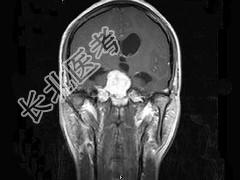

- 单项选择题女,32岁, 头痛、右侧肢体功能障碍约1年,声音嘶哑, 饮水呛咳,根据所提供图像, 最可能的诊断是 ( )

A、(斜坡)脑膜瘤

B、(斜坡)脊索瘤

C、(斜坡)神经鞘瘤

D、(斜坡)软骨瘤

E、(斜坡)海绵状血管瘤